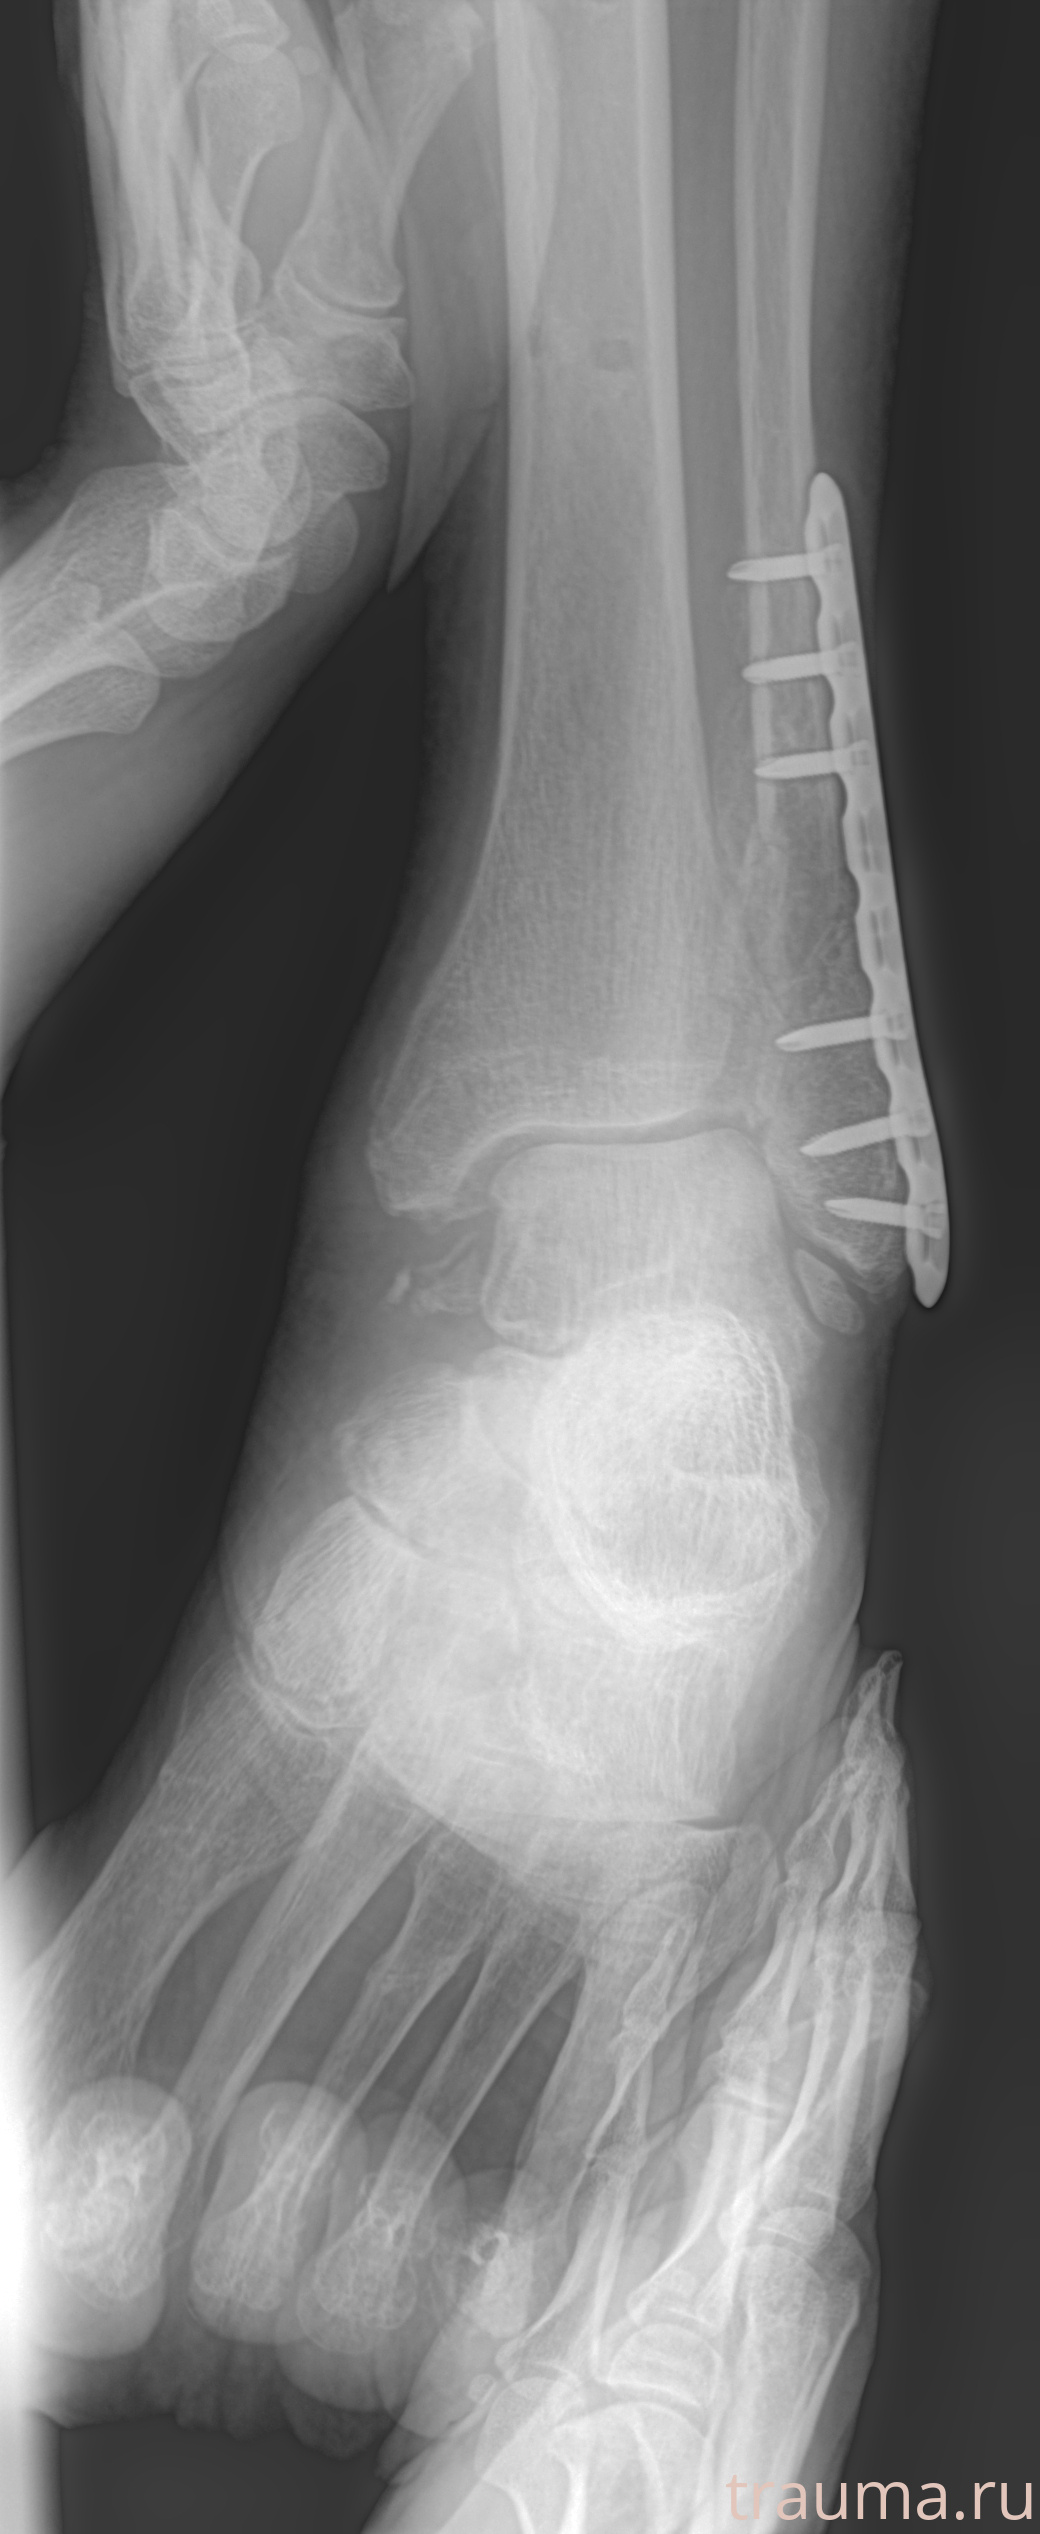

Рентген на дому: по вашему адресу приезжает врач-рентгенолог, травматолог-ортопед с мобильным рентгеновским аппаратом, проводит диагностику травмы или заболевания, делает необходимые рентгенограммы, дает рекомендации по дальнейшему лечению. Получить качественные снимки в домашних условиях возможно благодаря уникальной методике, разработанной МосРентген Центром для института  Склифосовского